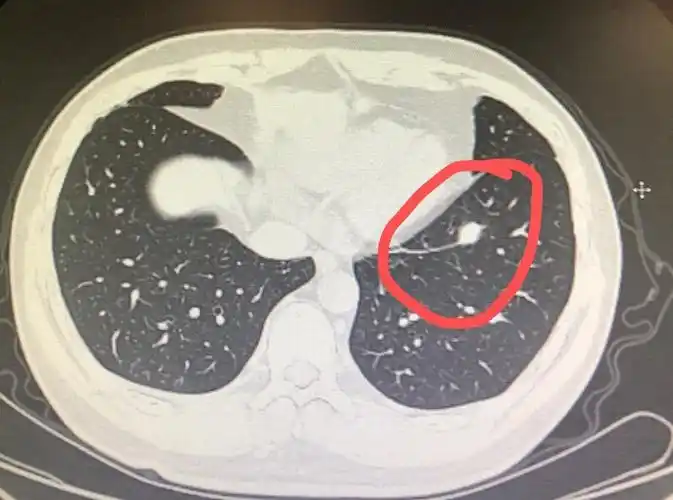

检查发现肺实性结节怎么办个人版实用指南

实性结节,内见点状钙化灶,外科医生说切,影像科医生说良性不用手术

通常情况下,实性结节和纯磨玻璃结节多为良性结节,部分实性结节是恶性